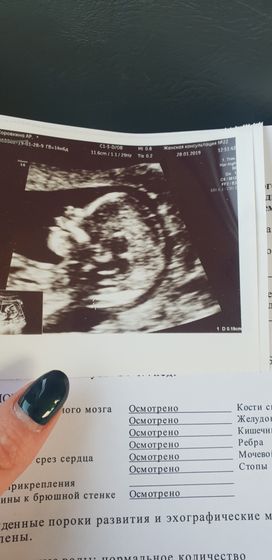

Пошла я сегодня на первый скрининг, думая с врачами, что у меня 12 нед 5 д, а оказалось, что прошляпили все благополучно. Нам уже 14 нед 1 д. 80%, что мальчик (я так и чувствовала прямо). Очень активные, вертлявые, достоинство свое со всех сторон показали ??? носастый и губастый))) жду теперь скорее второй встречи с роднулькой! Эмоции не передаваемые! Махали ручкой, показывали пятерню, открывали и закрывали рот))) только что не полмигивали)))

Ну я ей говорила, что дедушка девочку хотел. Она говорит, пока не расстраивайте его. Я спросила, насколько вообще вероятно, что точно мальчик? Она говорит, процентов на 80.

Ну потому что все равно на 100% судить вряд ли можно, наверно. Надо позже идти на 4d ущи и смотреть уже